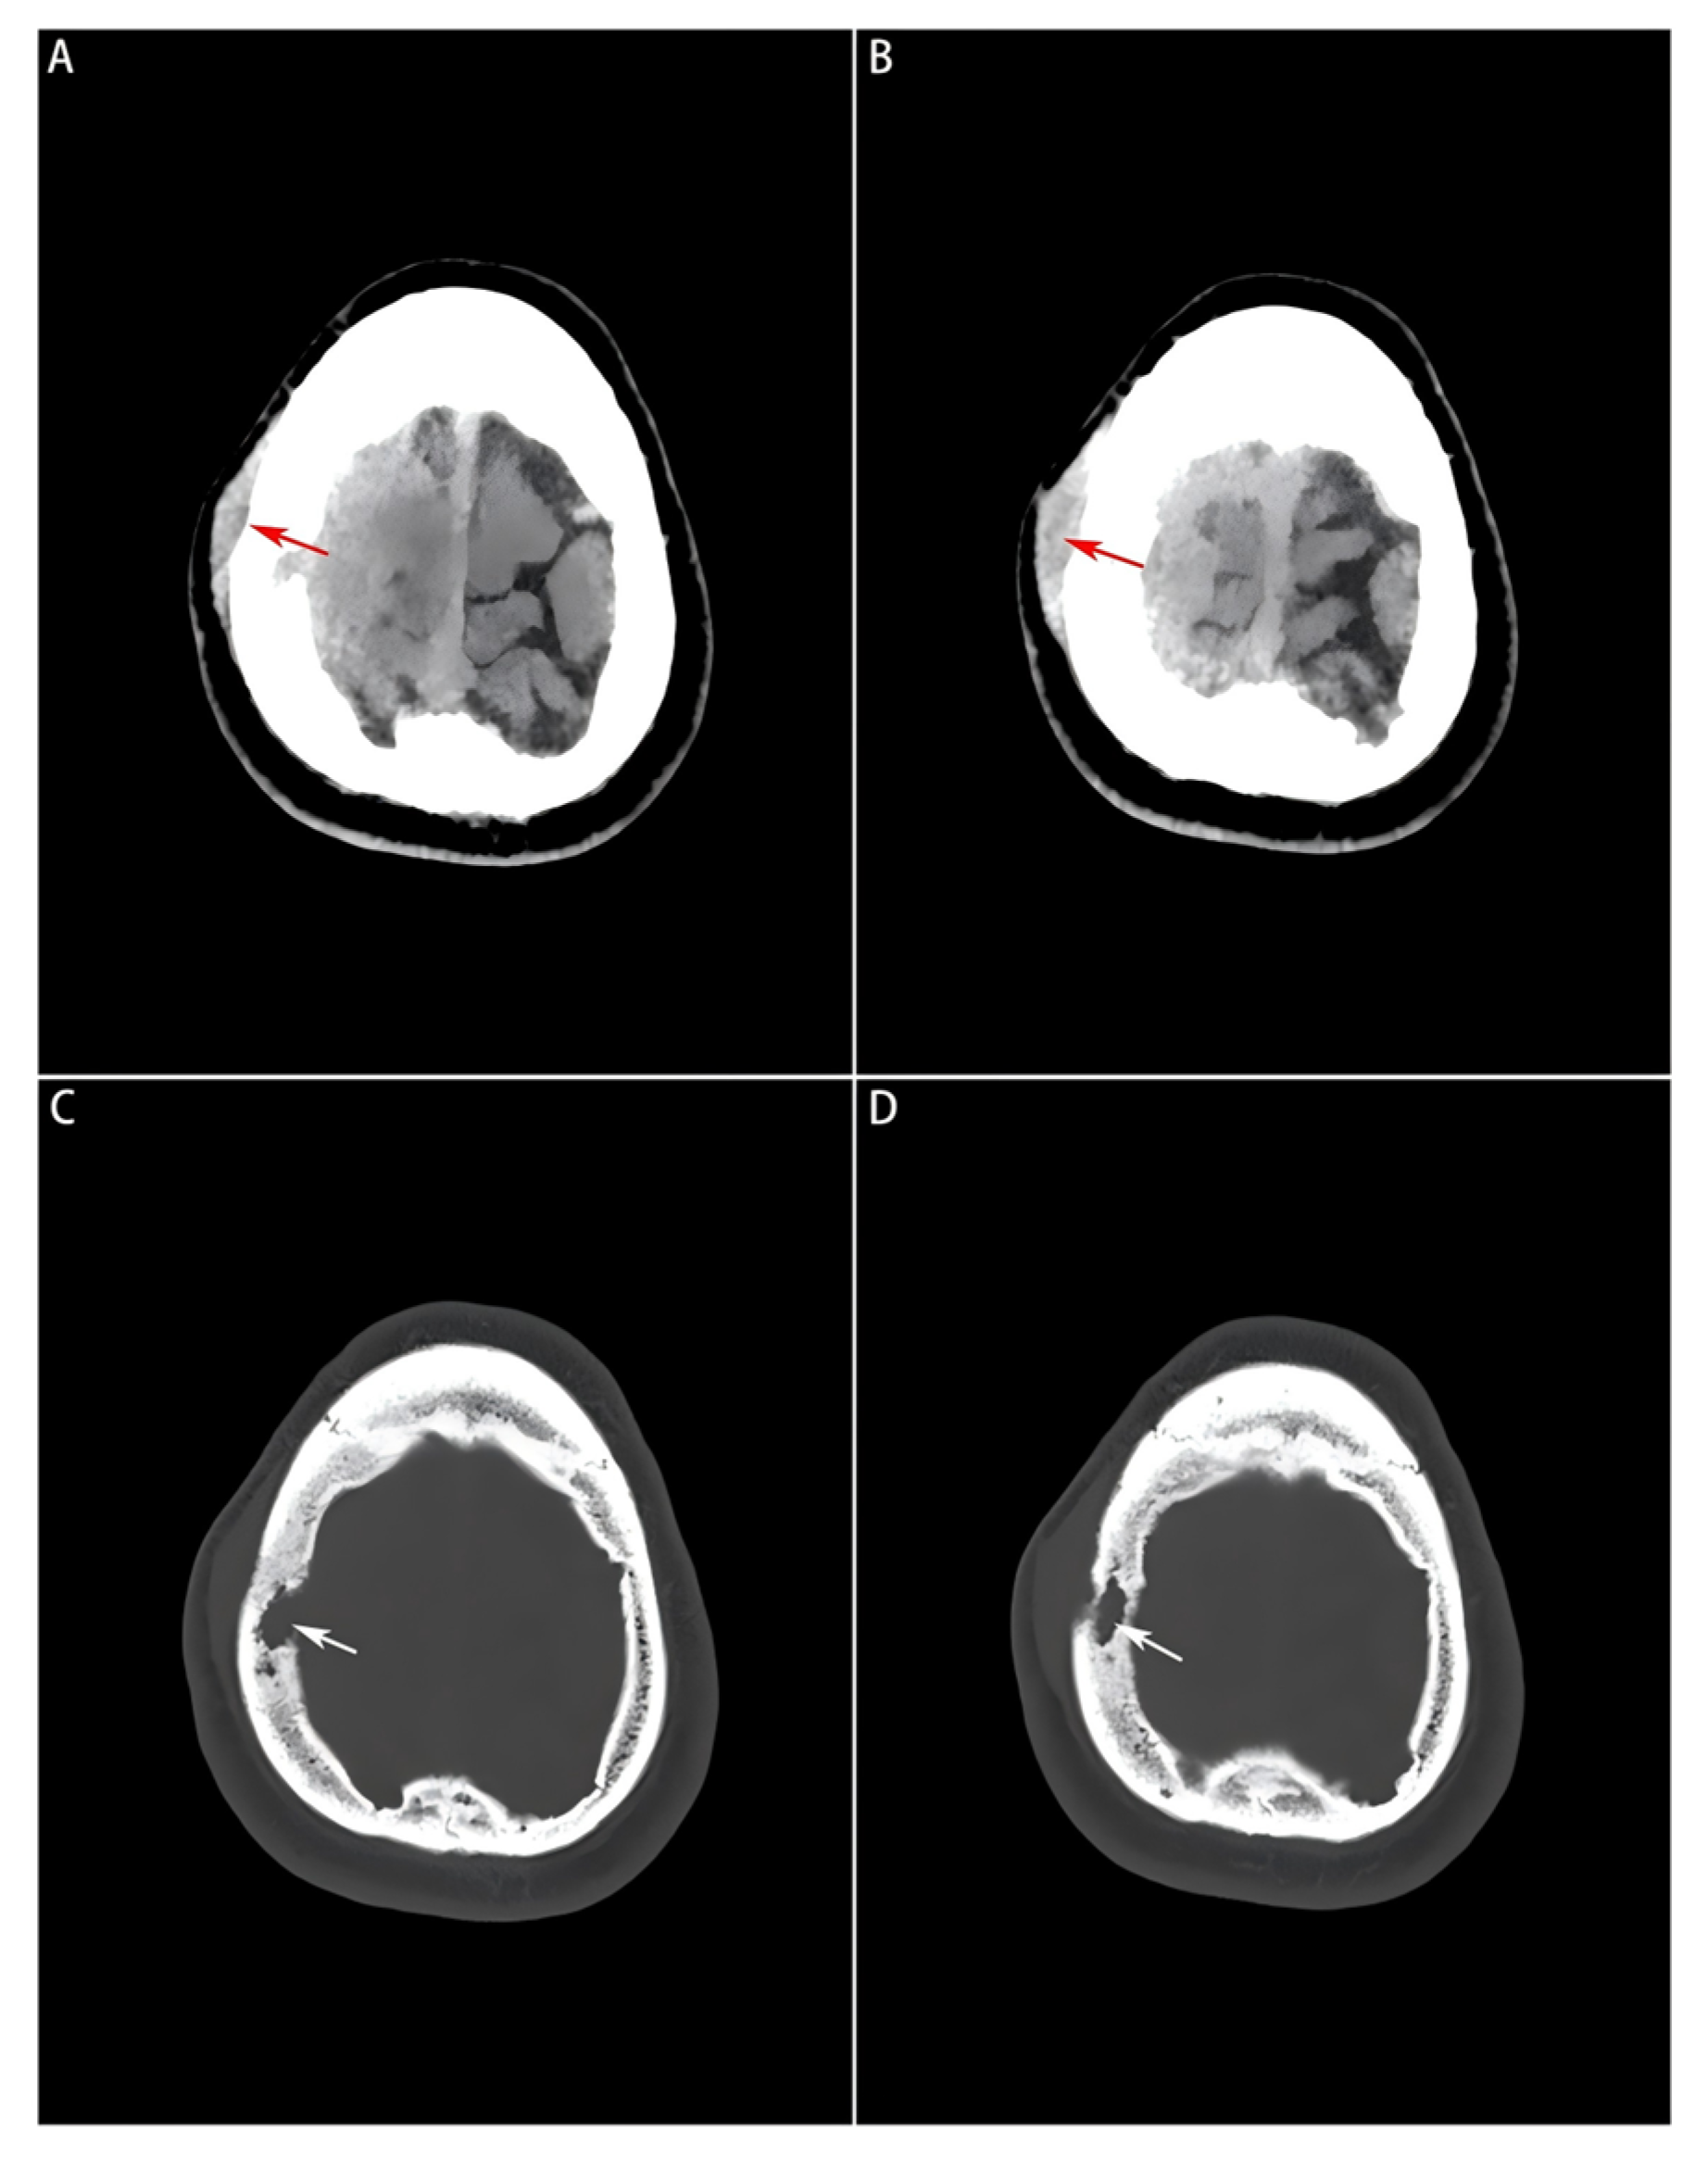

Head computed tomography (CT) scans (Philips Healthcare, Best, the Netherlands; software version R5.3) displayed a soft-tissue mass with a Hounsfield unit (HU) of 44, manifesting as a slightly high-density shadow in the right frontal lobe underneath the parietal bone, and compressed adjacent brain tissues (Figure 1A,B). Destruction of the right parietal bone was also seen on CT scans (Figure 1C,D). Nodular and strip-shaped thickening, uniform dural enhancement at the top of the right frontal, temporal and parietal lobes, and a spindle-shaped mass under the scalp with an abnormal cranial plate signal were found on preoperative contrast-enhanced magnetic resonance imaging (MRI) scans (Philips Healthcare, Best, the Netherlands; software version R6.1) (Figure 2A–D).

Figure 1.

Preoperative head CT images of the soft tissue window and bone window. (A,B): A slightly high-density mass visualized on the soft tissue window, where the subcutaneous mass formed by the tumor lesion invading outside the bone window is indicated by a red arrow; (C,D): Bone erosion and defect visualized on the bone window image, and localized by a white arrow.